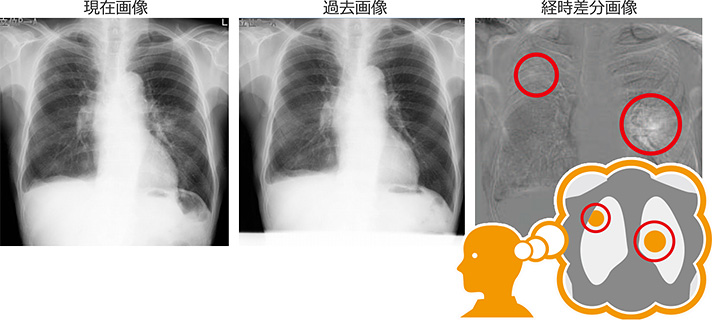

患者様の時間の変化を可視化する 「Temporal Subtraction処理」

比較読影用の胸部単純X線画像を並べた場合、先生方は頭の中で2枚の画像間の差をイメージして読影を行います。

それを瞬時に可視化する画像技術が「Temporal Subtraction(テンポラルサブトラクション/胸部経時差分)処理」です。

患者様の現在と過去の2枚の画像には、時間だけでなく、撮影機器のメーカーの違い、ポジショニングの違いなど、読影に不要な「差」も含まれています。

しかし、20年近くの開発期間をかけたコニカミノルタ独自のアルゴリズム補正は、患者様の状態の変化のみ、読影に必要な情報のみの出力を可能にしました。

継続して診察を行うかかりつけ医の先生方には、病巣の発見はもちろんのこと、肺炎の経過観察、異常所見のないケースを確認する場合にもご活用いただいています。